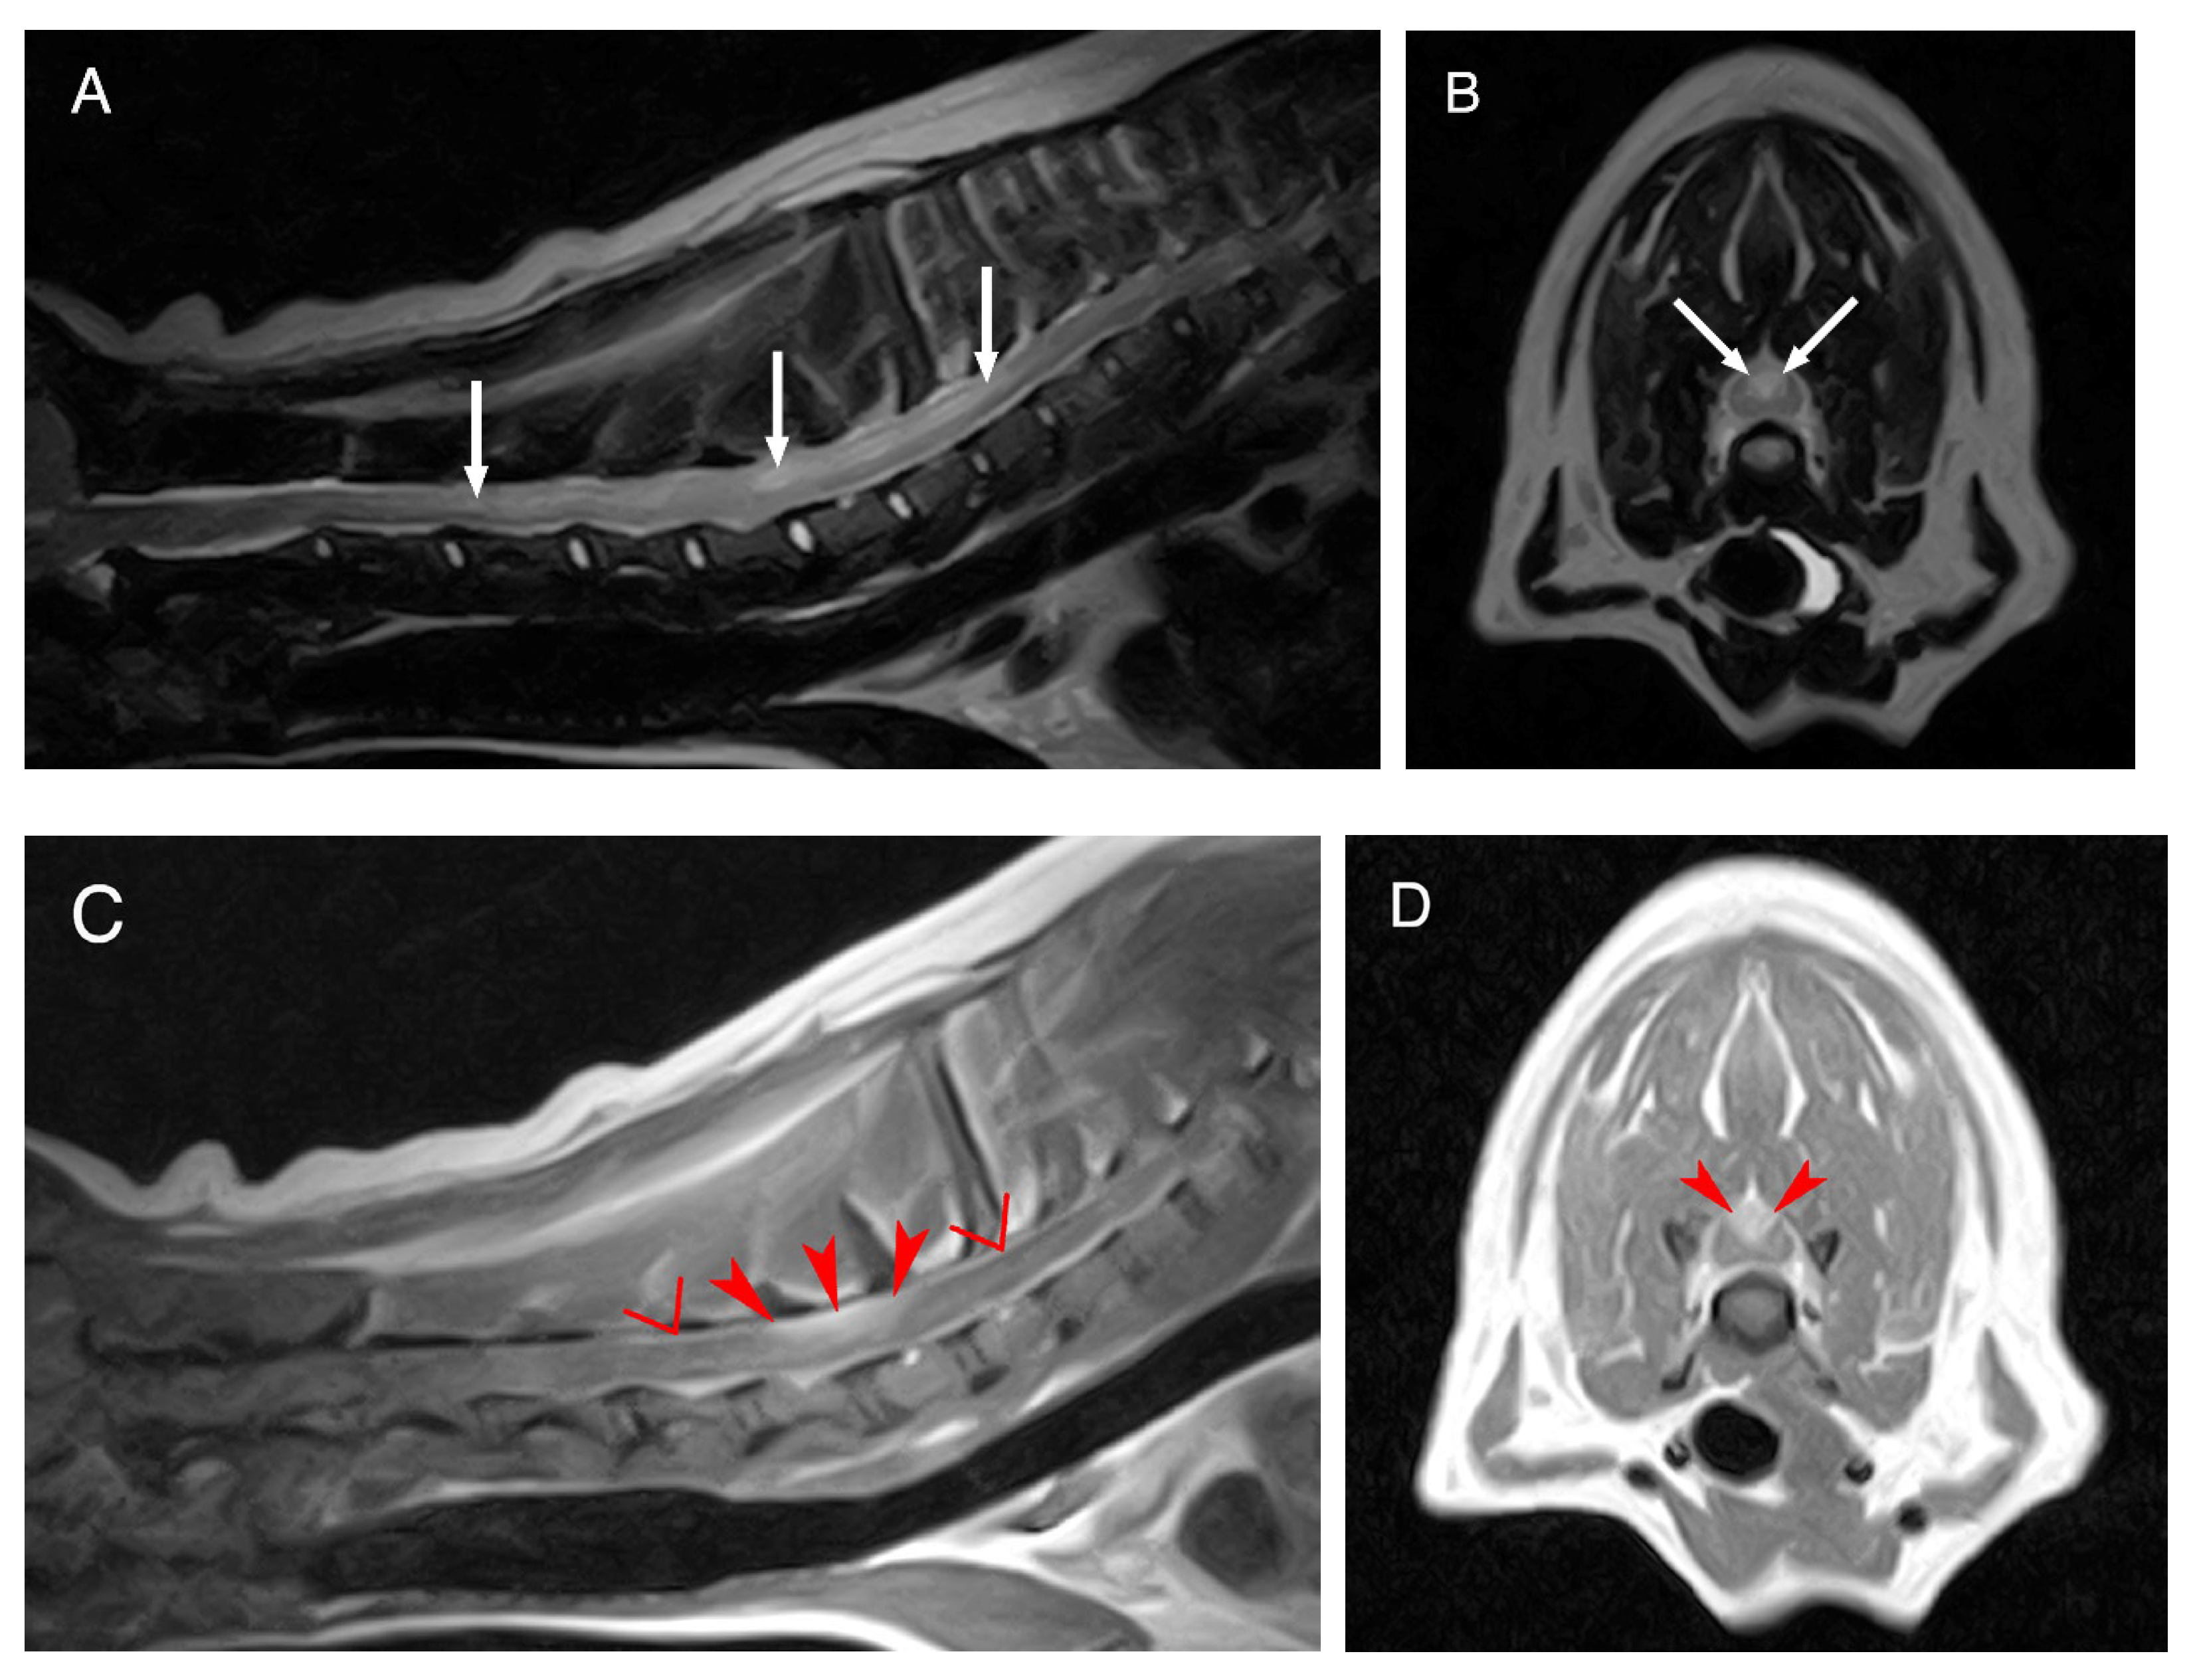

The complete blood count and serum biochemistry submitted by the referring veterinarian were within the normal limits. A low field MRI of the cervicothoracic region revealed an intramedullary lesion extending from C3 to T3, hyperintense on the T2-weighted (T2W) and isointense on the T1-weighted (T1W) sequences. This lesion was mildly lateralized to the left and affecting both the grey and white matter. Marked contrast enhancement was evident in the dorsal aspect of the spinal cord from C6 to C7. Meningeal contrast enhancement was also observed (Figure 1).

Figure 1.

MRI of the dog’s cervical region. Midsagittal T2W image (A), transverse T2W image at the level of C6–C7 (B), mid sagittal T1W post contrast image (C) and transverse T1W post contrast image also at the level of C6–C7 (D). The white arrows are pointing to the T2-weighted hyperintense, intramedullary lesion extending from C3 to T3. The red arrowheads show the marked contrast enhancement in the dorsal portion of the spinal cord at the level of C6–C7. The red inverted triangles show the meningeal contrast enhancement.